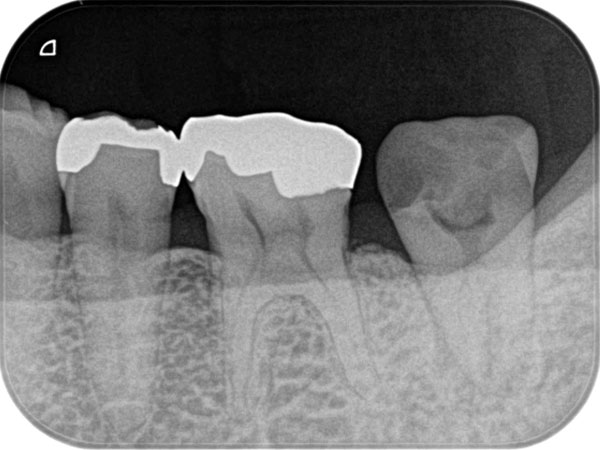

複雑な根管を治療するには、事前の画像診断で根管の形状を可視化することが重要です。多くの歯科医院では、画像診断に「2次元」のレントゲンが用いられますが、レントゲンでは初期の患部を見つけにくい上に、根管の複雑な形状をしっかり可視化するほどの力はありません。

そこで、当院では3次元で撮影ができる「CT」を利用します。CTはあごの骨の中を立体的に可視化するので、レントゲンには写らない患部の様子までがしっかりわかります。日本国内の歯科医院での、CTの普及率は5〜10%程度と言われています。